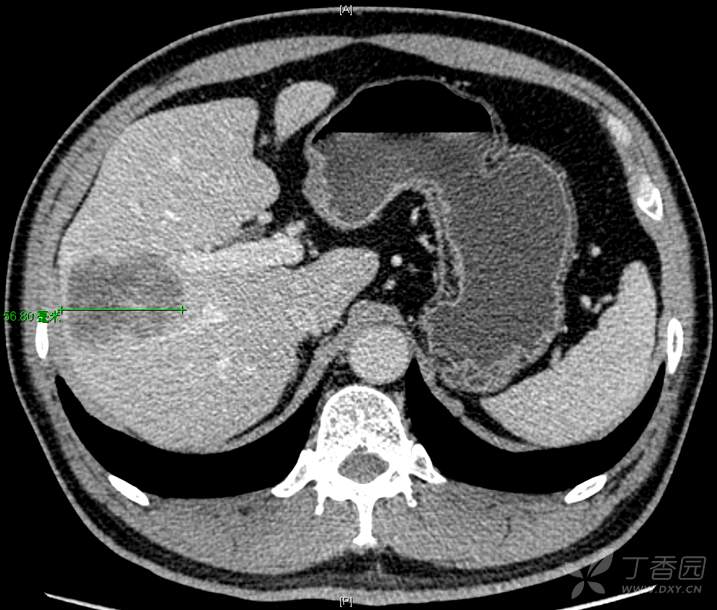

56岁男性,因右上腹隐痛不适检查发现右肝ICC可能于2021年11月来院。化验除了CA199>检测上限之外,无明显其他异常。影像报告:“右半肝可见一低密度肿块影,形态不规则,边界清晰,肿块内部密度不均匀,可见细小血管进入其中,增强扫描呈环形强化,大小约46mm×70mm×49mm,周围肝实质内可见异常灌注,局部肝包膜略回缩;病变周围可见多个类似卫星灶。门静脉不宽,肝内外胆管无扩张。胆囊不大,壁不厚,腔内未见异常密度影。”如下图: